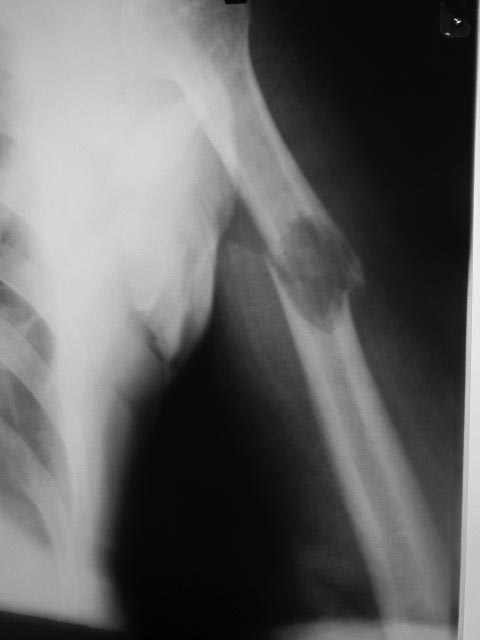

[Ortho] Патологический перелом плечевой кости

Уважаемые коллеги! Прошу высказать свое мнение по-поводу лечения

патологического перелома правой плечевой кости.

Больной 67 лет поступил в нашу РБ через два дня после травмы (падение с

дерева). В настоящий момент проходит обследование. Какую тактику

оперативного лечения вы посоветуете?